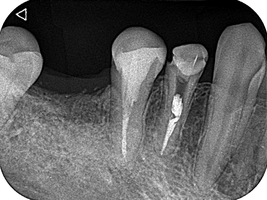

1回法で根管治療を終わらせてデンタルを撮影したところ、目を疑う光景がありました。

「6番の近心根がほぼそのまま残根しているぞ!…どうしよう」

根尖だけ若干残るのなら分かります。しかし、近心根がまるごと残っているのです。

これが日本よりも医療技術が進んでいる治療なのですか。

呆れて言葉が出ません。

患者さんに残根について説明し、限られたアポイントの中で、なんとか抜歯できました。